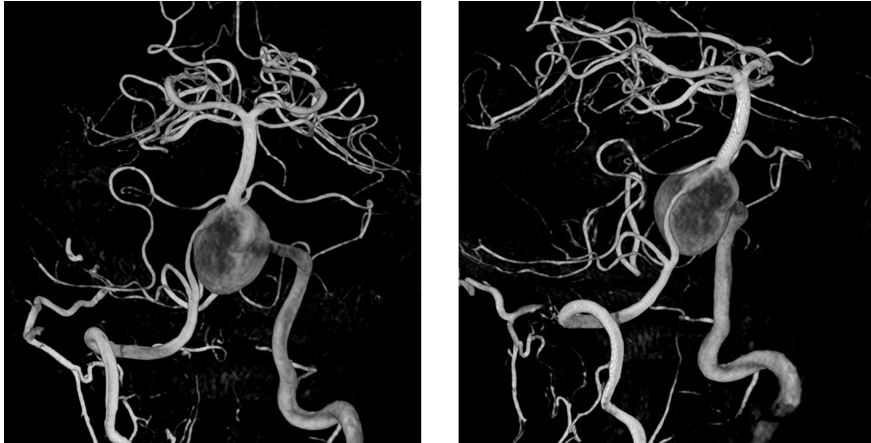

释放PED。由于瘤颈很宽,所以PED需要足够长,动脉瘤远端和近端才能具有足够的锚定力量,防止支架坠入瘤腔内。所以,我们选择了3.25*35mm的支架。支架上端定位在基底动脉中段

PED释放完毕,位置及贴壁良好,左椎-基底动脉血运通畅,未填弹簧圈,即可见到瘤腔内造影剂的滞留,说明支架贴壁良好,起到了良好的重建作用

经右椎动脉逐步填塞大弹簧圈进入动脉瘤(Microplex-18系列),逐步将动脉瘤疏松填塞。期间微导管头端受到弹簧圈阻力,会缓慢回撤,此时不必刻意调整微导管再次深入动脉瘤腔内,因为我们最主要目的不是严密填塞动脉瘤—那是PED的任务—而是闭塞右侧椎动脉

最后,用小弹簧圈完全闭塞右侧椎动脉(PICA以远)

左椎动脉造影显示椎-基底动脉及远端血管通畅,动脉瘤虽然部分显影,但是PED最终会让动脉瘤完全修复。